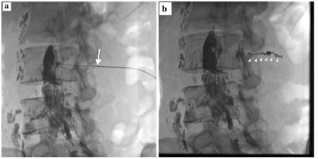

病例一女性 31岁,宫颈非典型腺细胞(atypical glandular cells AGC)术后腹胀

引流前和栓塞后 Drainage before and after embolization

- Amount: 4,200 ml → 150 ml

- Color: milky → serous